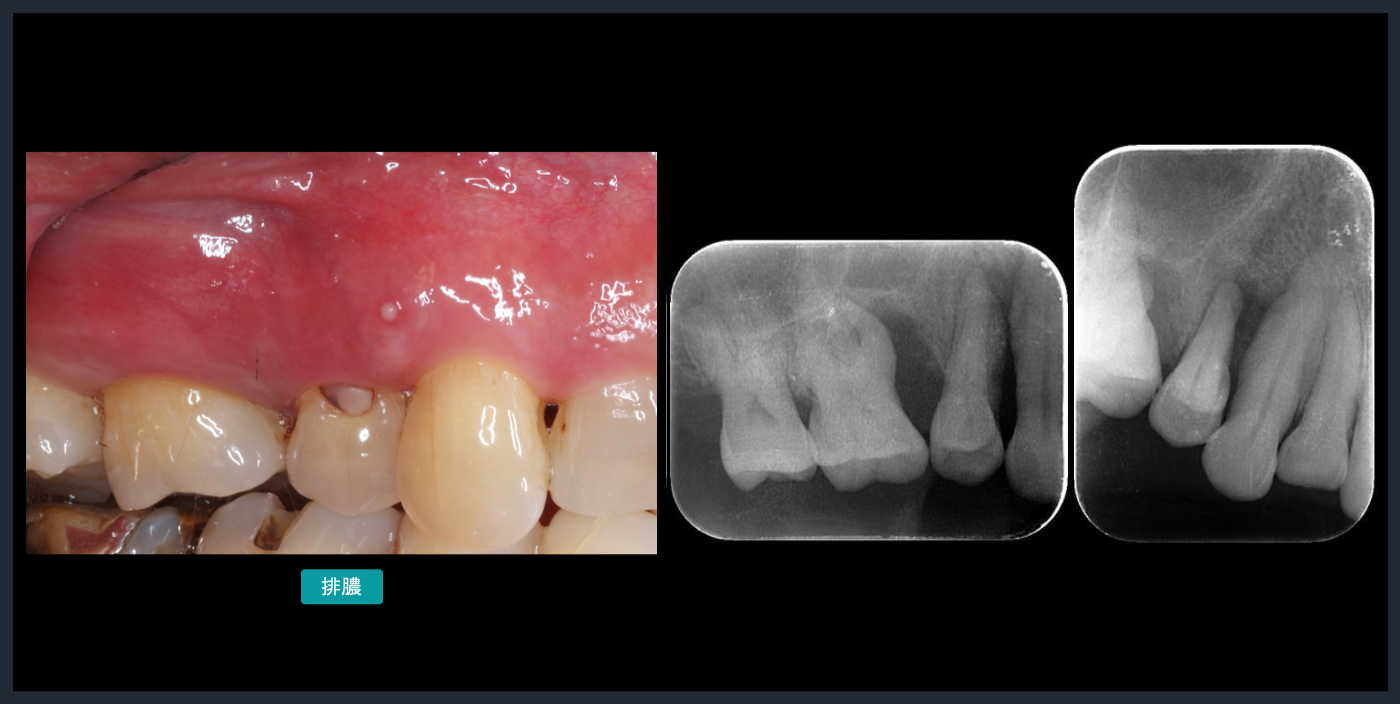

主訴‥「歯周病で歯茎が腫れている、物が食べづらい」

歯周基本治療中も、複数回の排膿を認めた。